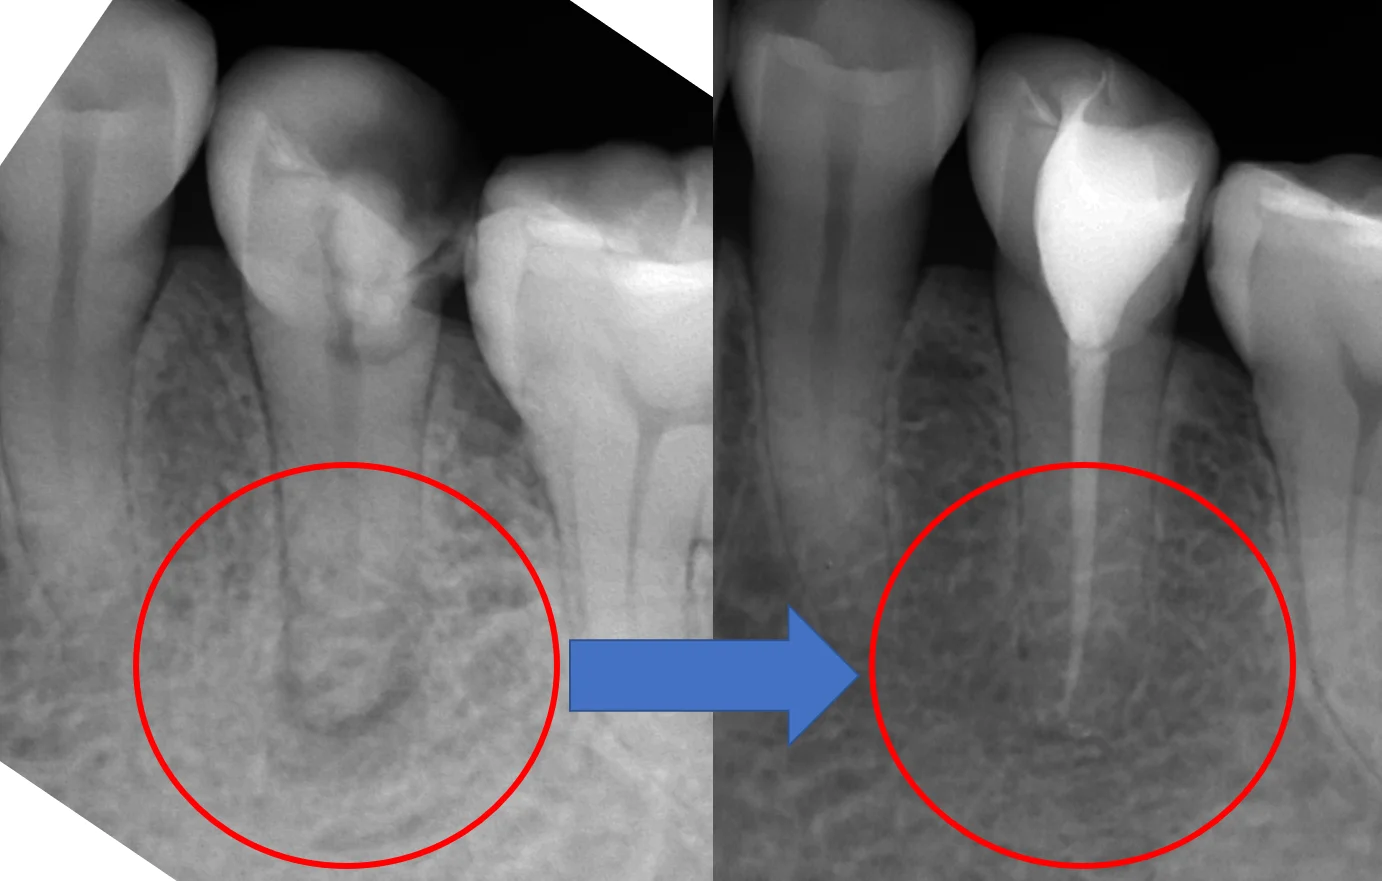

そして神経の治療後1年経過時のレントゲンがこちらです。

根の先に飛び出した薬剤はもちろん、骨にあった黒い影もほとんど消えています。

(あ、ちなみに、この方はそこそこ歯を残せたのでダイレクトボンディングで治療を終了させました。)

そして、術前術後がこちらです。

今回、非常に綺麗に治ってくれましたが・・・